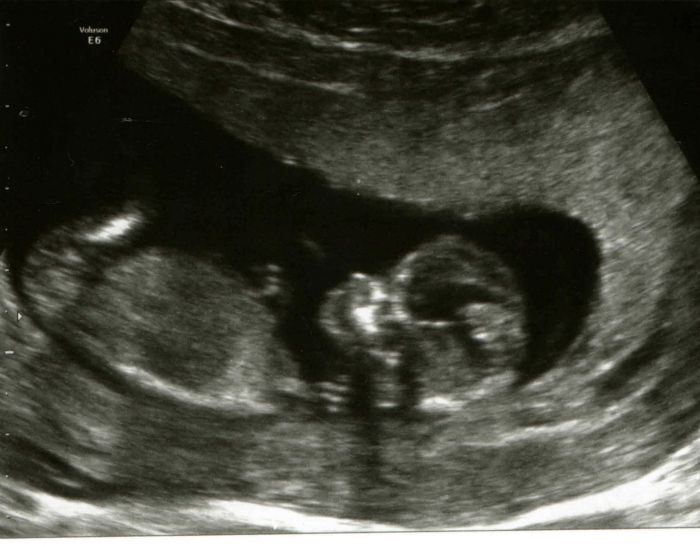

A holky, hlasim tedy, ze vcera na kontrole vse OK a posilam obrazek ;) Uz ma cca 8,3cm celkem  (+- ).

Jezisi to je krasny a jak to leti nejdrive fazolka a ted miminko krasne. No to verim. Na to.mi pomaha hodne sauna nejak me.drzi nad vodou no a.dokud muzu tak chodim